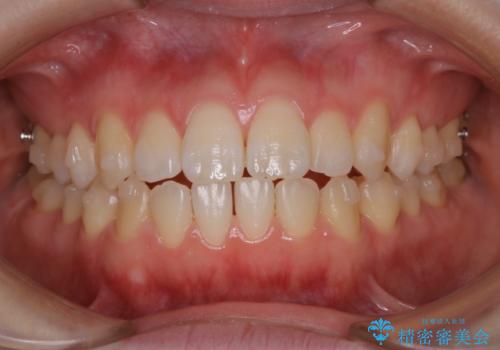

アタッチメント周囲のステインOFFをPMTC で

- インビザライン矯正治療中に、アタッチメント周囲のステインが気になるとのことでした。PMTC30分コースを行いました。

矯正治療中もPMTCを定期的に行い、専門的な機械でしっかりと汚れを除去することがおススメです。